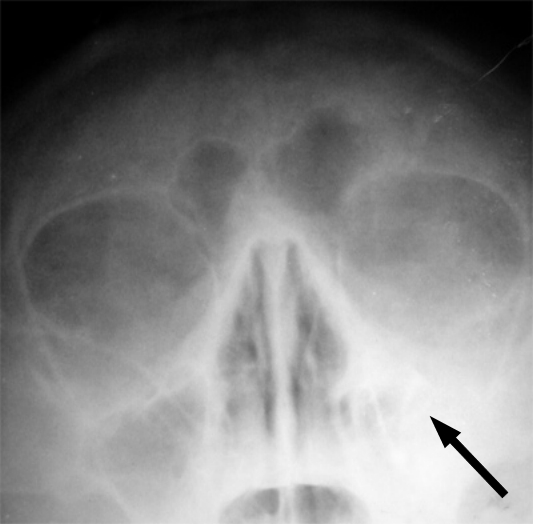

Mittlerweile aber gibt es so viele gute klinische Studien, die folgendes zeigen: Bei PatientenInnen mit Sinusitis (Nasennebenhöhlenentzündung) helfen Antibiotika nicht. (Der Grund: Antibiotika können bei Sinusitis nicht helfen, weil diese Krankheit gar nicht durch Bakterien verursacht wird.) Die Sendung erklärt den Unterschied zwischen Bakterien und Viren.